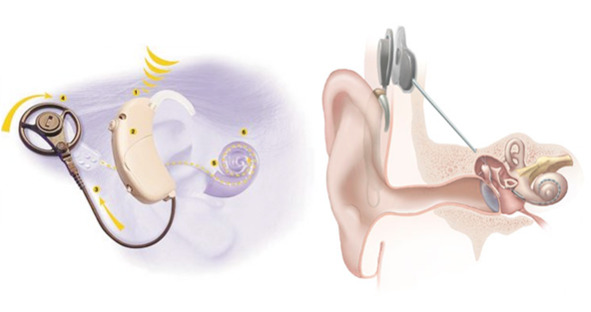

Кохлеарный имплантат

Кохлеарный имплантат

Кохлеарный имплантат – медицинский прибор, протез, позволяющий компенсировать потерю слуха некоторым пациентам с выраженной или тяжёлой степенью нейросенсорной (сенсоневральной) тугоухости.